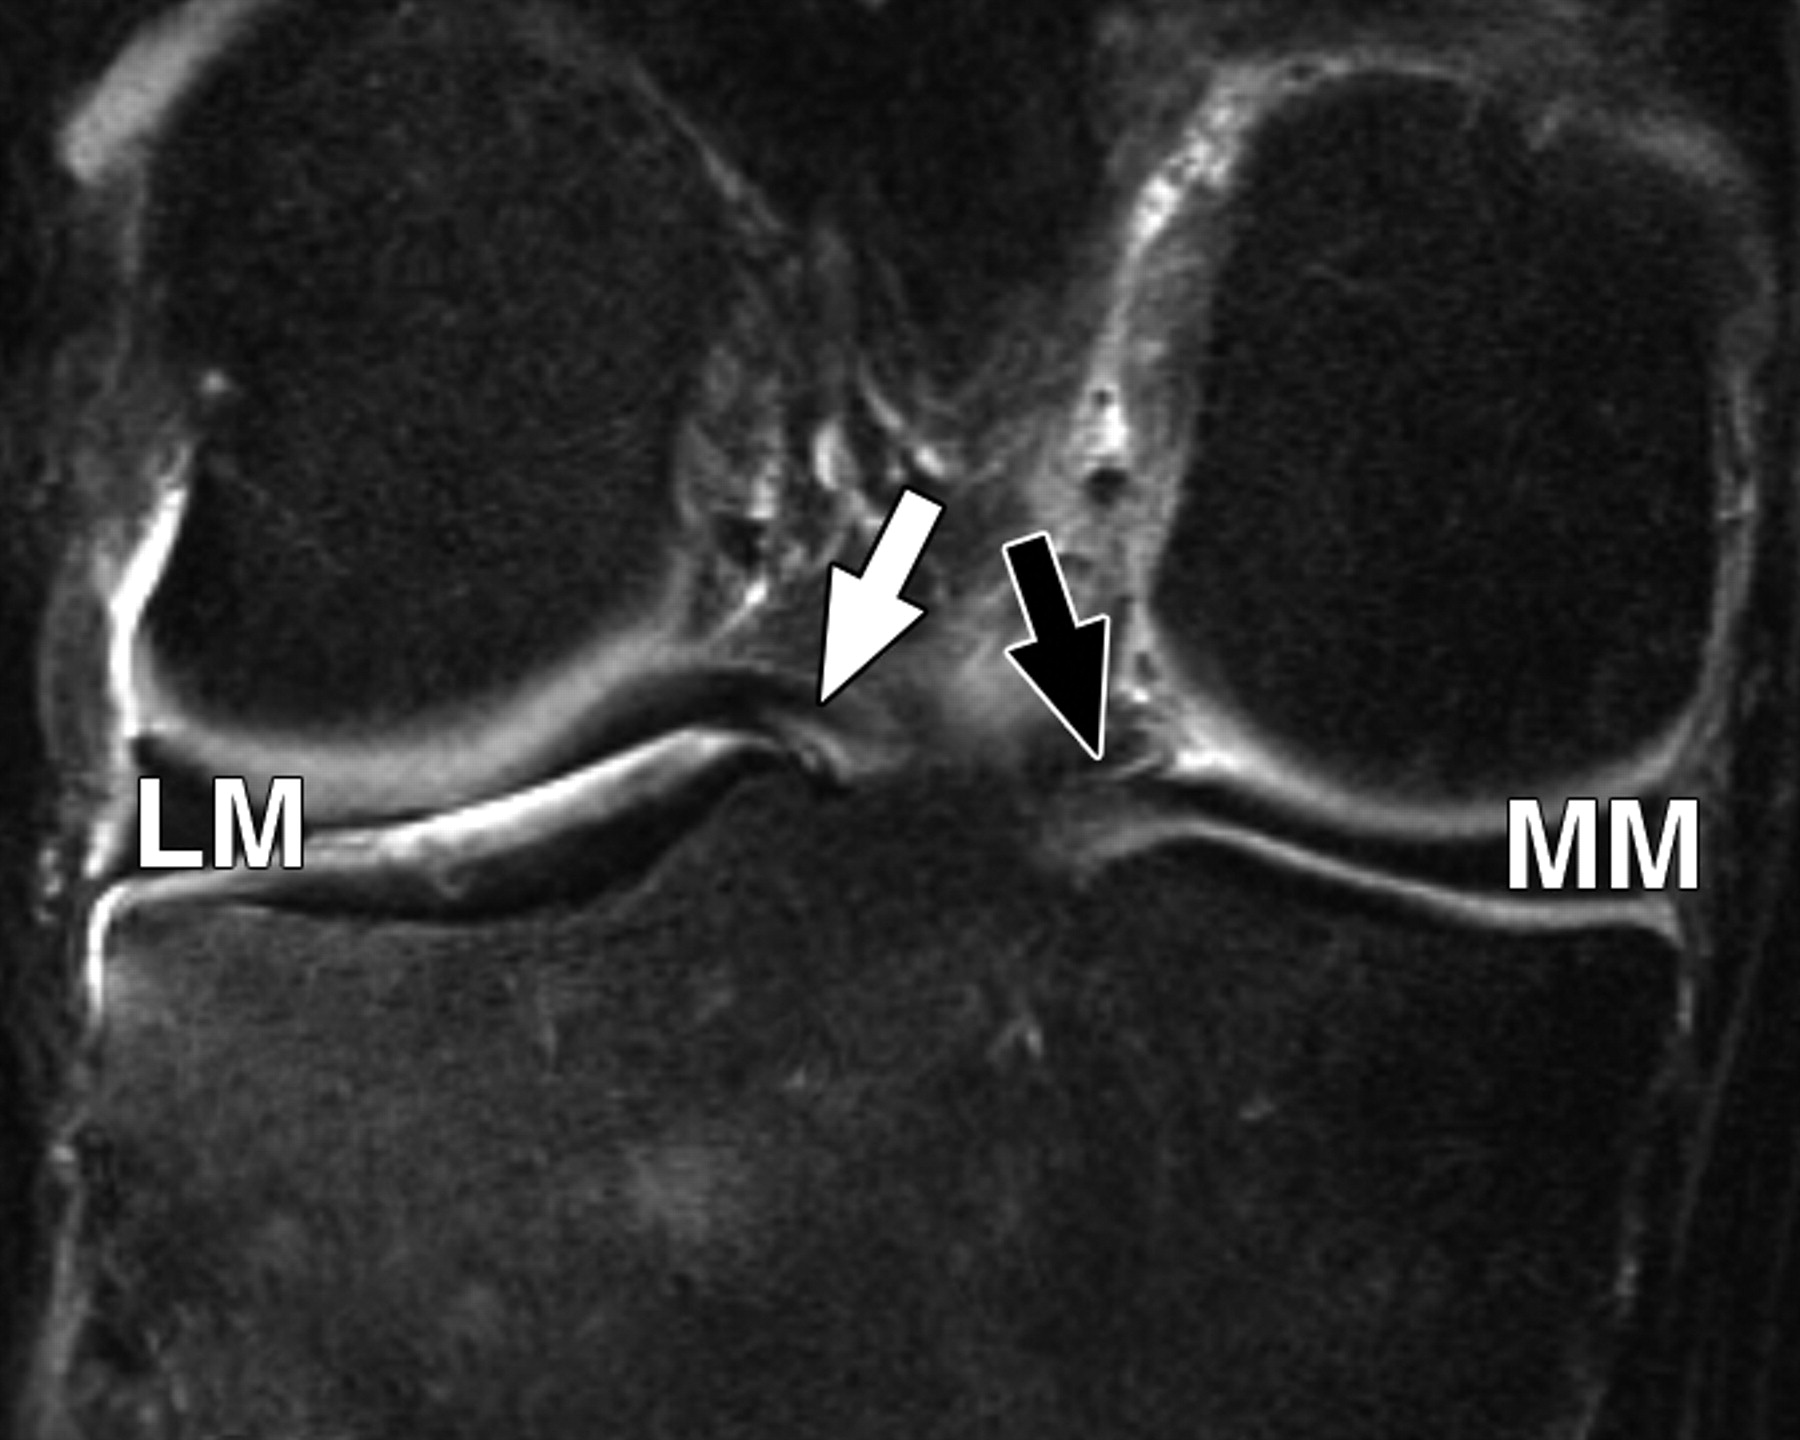

图5 B-59岁男性。中等加权、脂肪饱和、快速自旋回波(TR/TE有效值,3,700/29)3-T MR图像显示半月板后根和交叉韧带的解剖关系。

冠状面图像依次位于A的腹侧,显示外侧半月板后根(LM)(白色箭头)和内侧半月板后根(MM)(黑色箭头,B)的插入,覆盖后髁间区域的一个以上切片厚度。MT =胫骨内侧结节。

图5C-59岁男性,中等加权、脂肪饱和、快速自旋回波(TR/TE有效值,3,700/29)3-T MR图像显示半月板后根和交叉韧带的解剖关系。